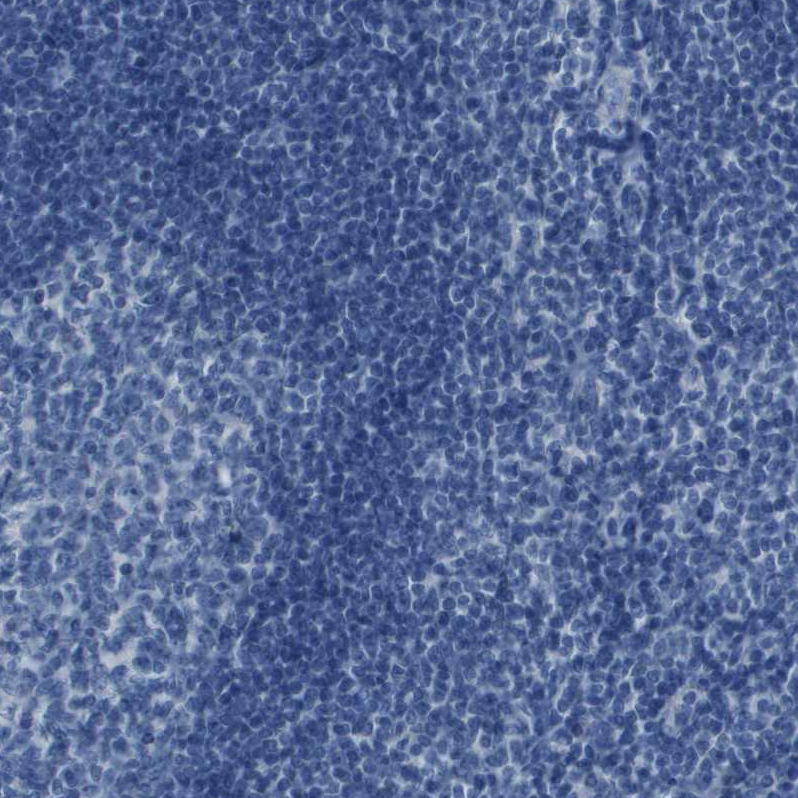

Immunohistochemistry analysis in human kidney and pancreas tissues using HPA017053 antibody. Corresponding CDHR2 RNA-seq data are presented for the same tissues.